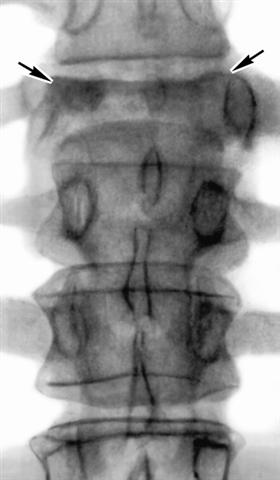

Рис. 3а). Рентгенограмма позвоночника при туберкулезном спондилите (прямая проекция): обширная деструкция тела XII грудного позвонка (указан стрелками) с его клиновидной деформацией и скобкообразными тенями оссификации в переднебоковых отделах.